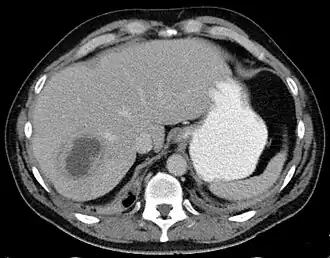

![]() Absceso hepático en la imagen axial de TAC: una lesión hipodensa en el hígado con realce periférico. | ||

En el ultrasonido se mostrará una masa quística en el hígado que tiende a ser septado o bien con características homogéneas. Si se hace una tomografía axial computarizada (TAC), se apreciará una masa hipodensa (oscura) con bordes precisos.[10] La aspiración percutánea del absceso y su cultivo microbiológico es esencial para el tratamiento adecuado y el drenaje del absceso. Con frecuencia se instala un catéter de drenaje, en especial para pacientes con abscesos complejos o que contengan fluido muy espeso. Los abscesos múltiples son comunes en pacientes inmunosuprimidos y se debe considerar varios organismos etiológicos, incluyendo una candidiasis.